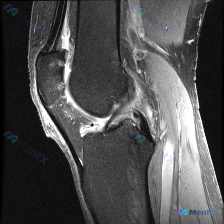

病例读片分享:膝关节MRI软骨异常的矛盾结果 刚整理了一份很有意思的读片病例,原提问说这张影像存在软骨异常,但我们完整分析完,结果和提问的判断矛盾,给大家分享一下整个过程。 影像基本信息 这是一张膝关节MRI冠状位影像,考虑是质子密度加权(PDWI)序列,这类序列分辨率高,非常适合观察膝关节的半月板...

刚整理了一个有意思的读片病例,临床和影像表现有点冲突,分享一下完整分析思路: 病例基础信息 这是一张膝关节MRI冠状位T1加权成像(T1WI),用户提示观察内容为「软骨异常」。 影像读片结果 先给大家说清楚各个结构的观察情况: 1. 骨骼结构:股骨远端、胫骨近端显示清晰,骨皮质低信号、骨髓腔中等信号...

看到这个病例很有代表性,整理了完整资料和分析思路分享给大家 病例与影像资料 本次评估的是单张膝关节MRI T1加权序列冠状位图像,临床提出问题:影像是否存在软骨异常? 对影像的详细评估结果如下: 1. 骨骼系统:股骨远端、胫骨近端骨皮质连续,无骨折,骨髓信号正常,无局灶低信号,无骨质破坏、囊变或骨赘...